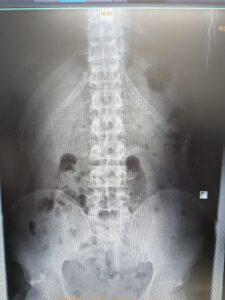

当院放射線科の特徴は、単純XP撮影での撮影・骨密度検査・超音波検査(エコー)などの画像診断を担当しています。撮影・検査後の画像や読影診断レポートを電子カルテと共有し、迅速な治療方針の決定に大きく貢献しています。骨密度検査は精度の高い骨密度測定器を導入しています。また、超音波検査(エコー)は、頸動脈(動脈硬化)・甲状腺・腹部等の検査を行っています。検査をご希望の方は、お電話でご連絡いただくか、お気軽にスタッフにお尋ねください。